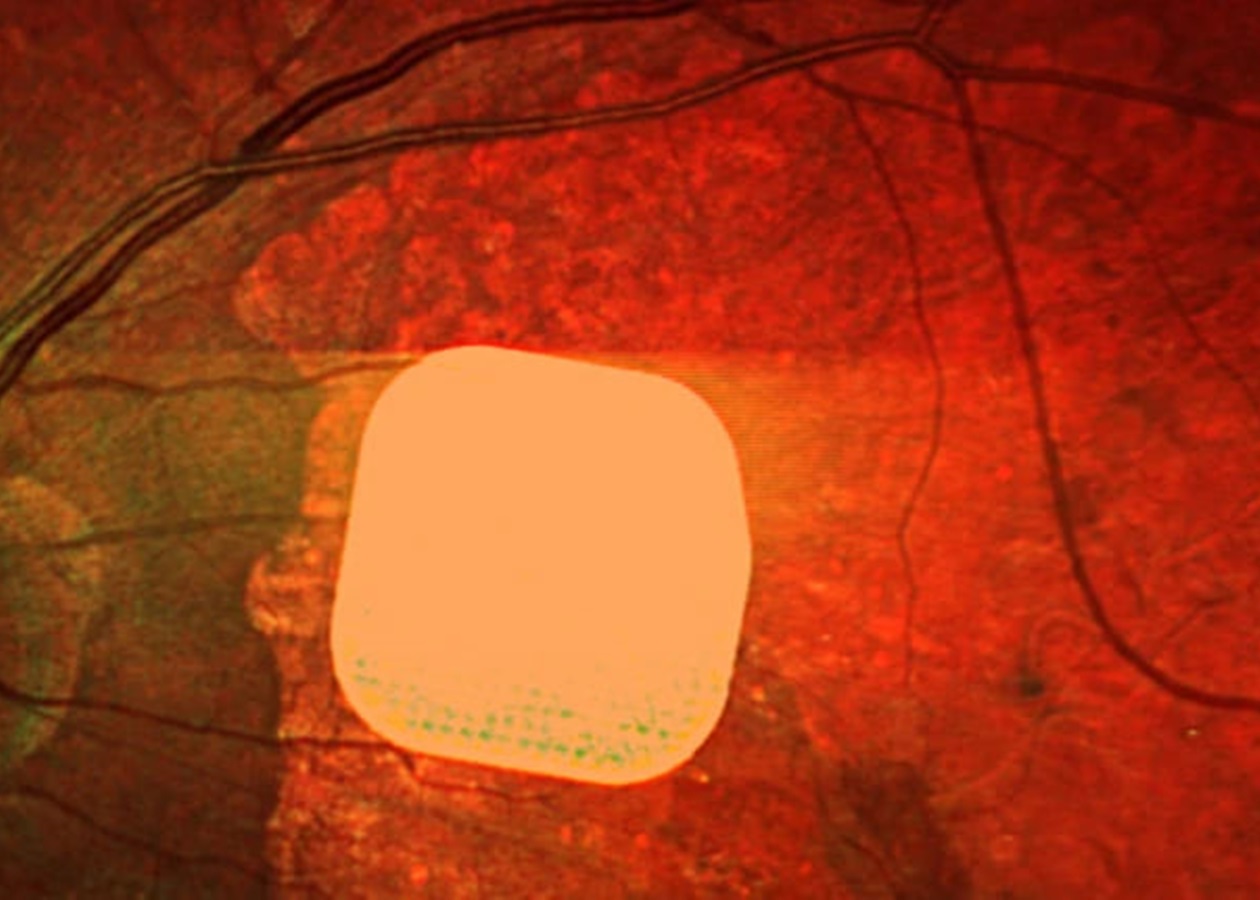

Мікрочип розміром лише 2×2 міліметри і завтовшки з половину людської волосини хірургічно встановлюють під сітківку ока. Під час операції, що триває менше двох годин, пацієнту також під’єднують систему окулярів доповненої реальності з камерою і мінікомп’ютером. Камера зчитує навколишнє зображення, перетворює його на інфрачервоний сигнал і передає на мікрочип, який активує клітини сітківки. Потім через зоровий нерв сигнал надходить до мозку, утворюючи візуальне сприйняття.

У дослідженні взяли участь 38 пацієнтів із “сухою” формою вікової макулодистрофії. До операції вони повністю втратили центральний зір і могли бачити лише периферійно. Після імплантації та періоду адаптації 84% учасників знову змогли розрізняти літери, цифри та слова.